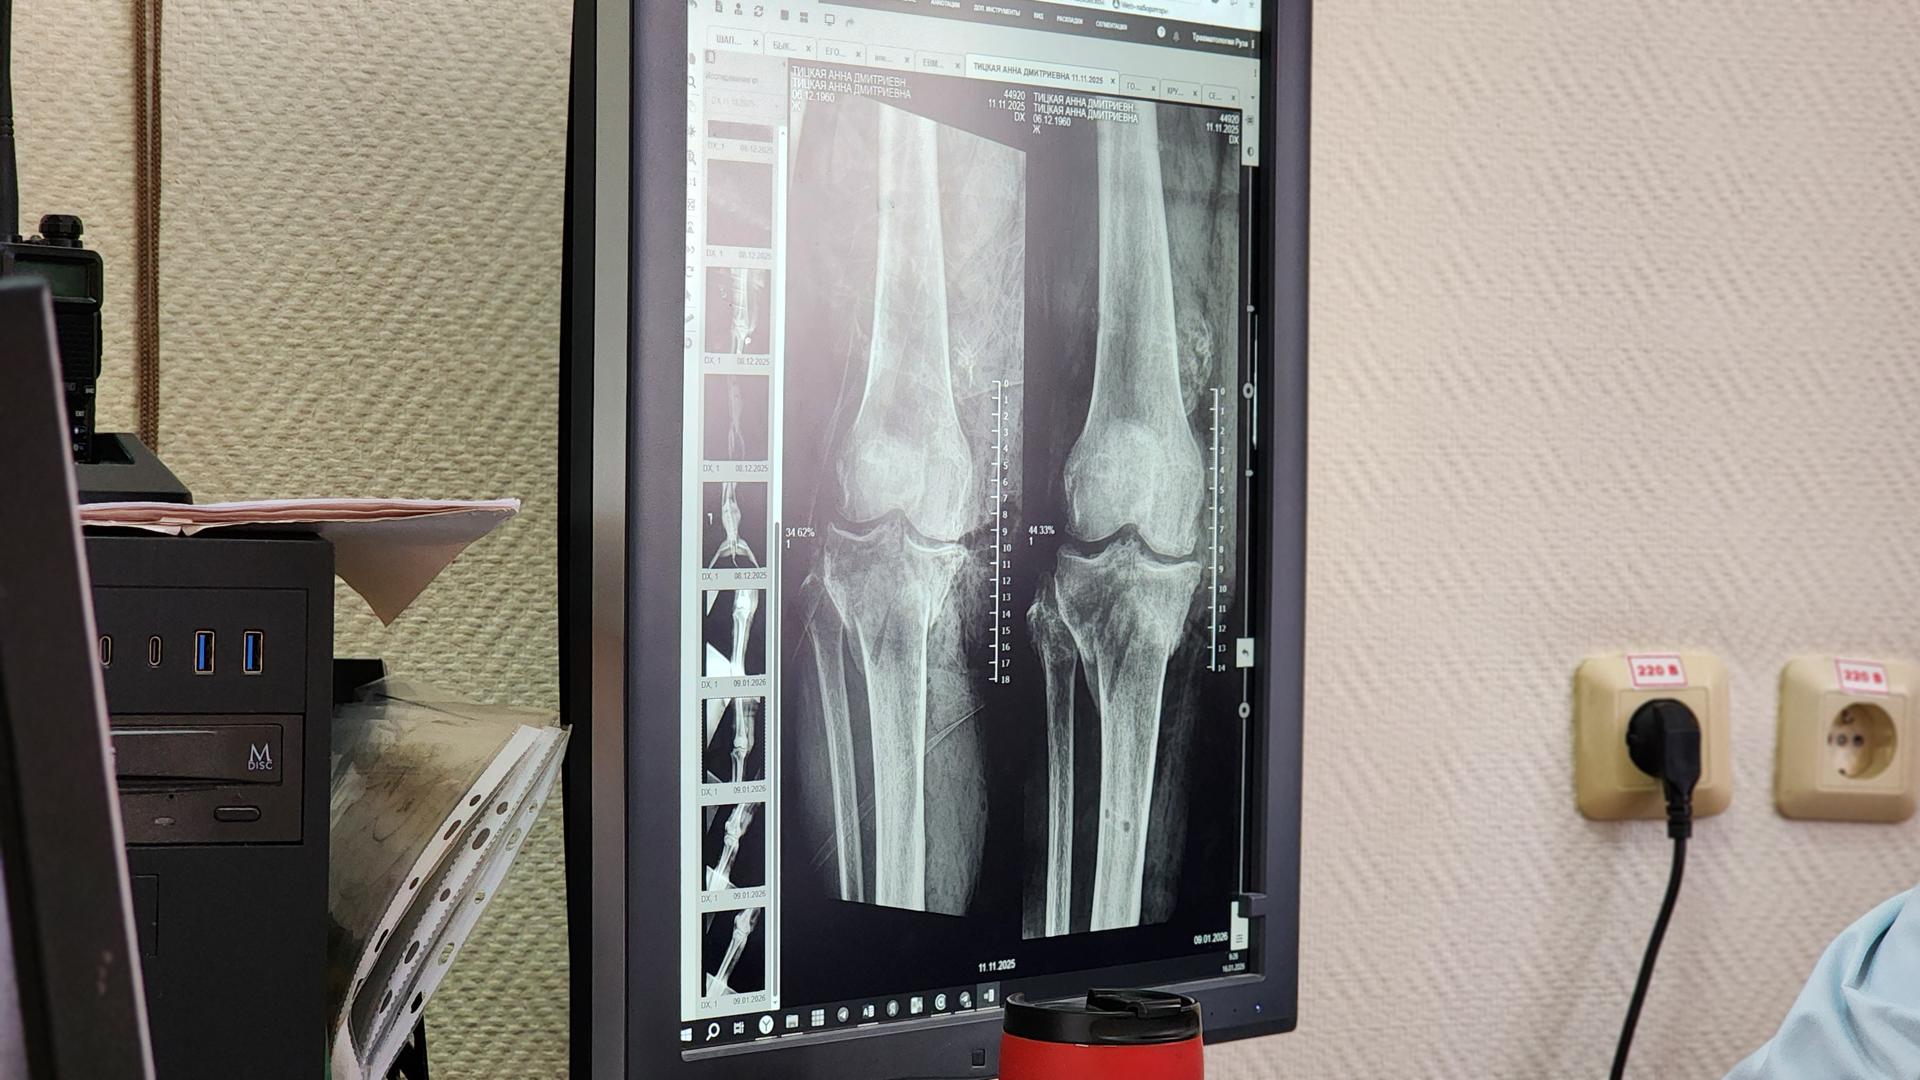

Трагедия оборвала привычный ход жизни в один миг: после наезда багги она получила открытый перелом обеих костей правой голени со смещением и обширную рваную рану под коленом. В стационаре Рузы опытные травматологи-ортопеды сразу же установили фиксирующий аппарат, наложили швы и, как истинные художники, бережно восстановили кожный покров с помощью пластики.